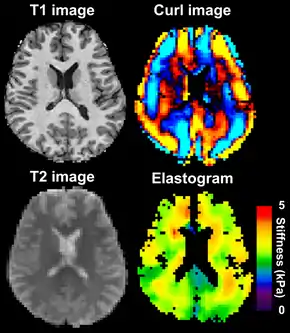

Magnetic resonance elastography of the brain. A T1 weighted anatomical image is shown in the top-left, and the corresponding T2 weighted image from the MRE data is shown in the bottom-left. The wave image used to make the elastogram is shown in the top-right, and the resulting elastogram is in the bottom-right.

MRE is conducted in three steps: first, a mechanical vibrator is used on the surface of the patient's body to generate shear waves that travel into the patient's deeper tissues; second, an MRI acquisition sequence measures the propagation and velocity of the waves; and finally this information is processed by an inversion algorithm to quantitatively infer and map tissue stiffness in 3-D.[2][3] This stiffness map is called an elastogram, and is the final output of MRE, along with conventional 3-D MRI images as shown on the right.[2]